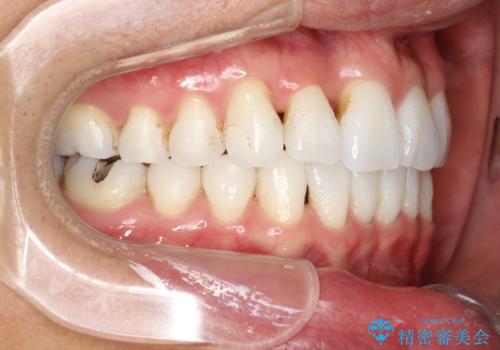

インビザライン終了時のPMTC

PMTC60分1万円+tax(保険適応外)を行いました。

インビザライン矯正治療は、歯にアタッチメント(歯を動かすための突起物)をつけます。そのため、矯正治療が終了し、アタッチメントを外すと着色が目立つことがあります。矯正治療の終了のタイミングではクリーニングを行い、着色の除去や歯と歯の間・歯と歯肉との境目などのケアをしっかりすることをおすすめしています。